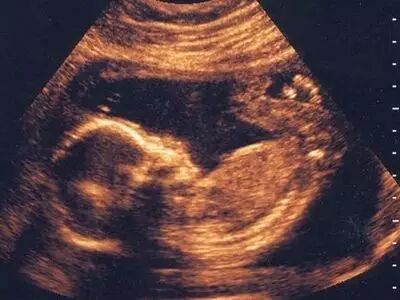

爱德生引进最新的美国GE-E8四维彩超,可以清楚地看到宝宝在妈妈肚子里的一举一动。

我院彩超医生经验丰富、耐心诊断,更加准确、直观、快读的知晓胎儿的状况,给予准妈妈们最准确的意见。